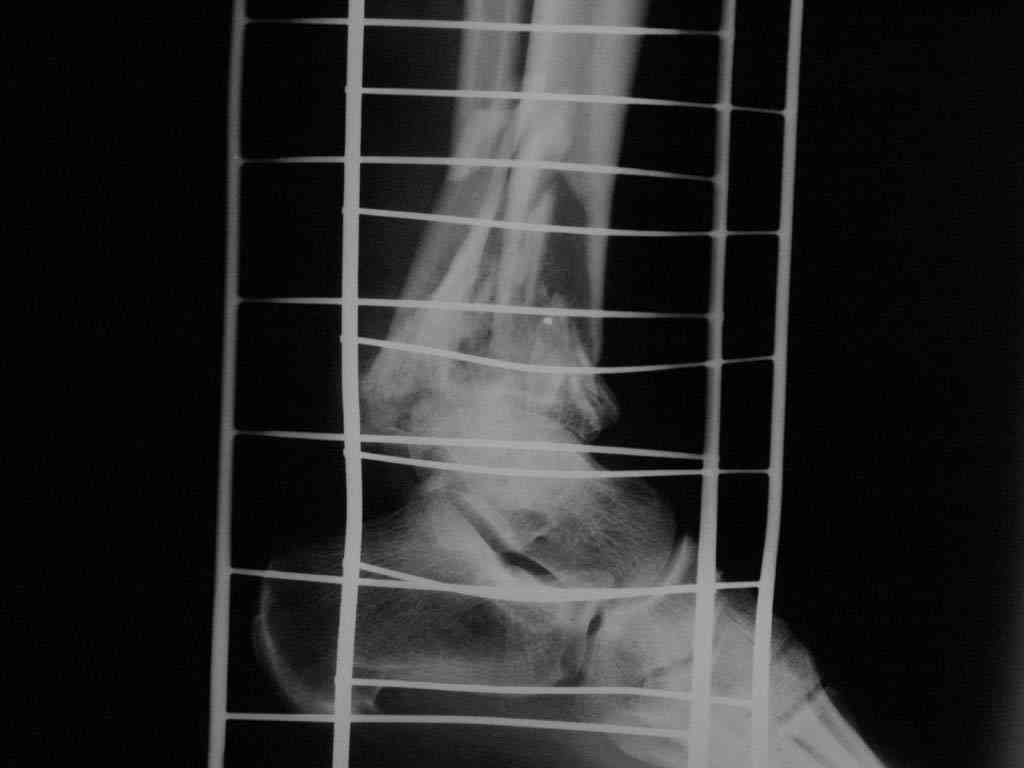

|  |  |  |  status localis на 14.11.08 (В ране визуализируется сухожилие.) | Больной А, 40 лет, находится в клинике с 15.10.08 с диагнозом: Сочетанная травма. Ушиб головного мозга лёгкой степени тяжести. Компрессионные переломы тел 12 грудного и 5 поясничного позвонков без неврологических осложнений. Закрытый внутрисуставной многооскольчатый перелом дистальных метаэпифизов обеих костей правой голени со смещением. Открытый внутрисуставной многооскольчатый перелом дистальных метаэпифизов обеих костей левой голени со смещением (см. Р-граммы). Хронический алкоголизм. Доставлен СМП после падения с 5-го этажа (не суицид). При поступлении состояние тяжелое. Глубокое оглушение. Дыхание самостоятельное, адекватное. Гемодинамика стабильная. По внутренней поверхности левой голени, в нижней трети, рвано-ушибленная рана 10-6 см, из раны выстоит проксимальный отломок большеберцовой кости, рана обильно загрязнена землёй. Интенсивная терапия в условиях реанимационного отделения, вытяжение за правую пяточную кость, параартериальная блокада обеих нижних конечностей, гипсовая лонгета на левую нижнюю конечность, ас-повязка на рану. Через 4 часа после поступления оперирован: после неоднократного промывания раны тёплой проточной водой с мылом, антисептиками, при ревизии определяется земля в канале проксимального отломка на глубину 3 см..., отсутствие надкостницы на концах дистального и проксимального отломков на 3 см. Удалено значительное количество мелких костных фрагментов, перемешанных с землёй, выполнена ПХО раны, резекция проксимального конца большеберцовой кости на 3,5 см, ЧКДО аппаратом Илизарова. Рана не ушивалась. В последующем перевязки раны с "Левомеколь", через 3 недели с момента травмы в ране определялись грануляции, нежизнеспособный конец дистального отломка. 10.11.08 ВХО раны, резекция дистального отломка на 3 см, перемонтаж аппарата наружной фиксации (см. Р-граммы). Отломки сближены на 2 см (остеотомию малоберцовой не делали). В настоящее время (5 сутки после операции) незначительное количество серозного отделяемого из раны, имеется дефект кости 4 см (см. Р-граммы). В последующем склоняемся к перемонтажу аппарата наружной фиксации, остеотомии малоберцовой кости в области повреждения, сближении отломков. По заживлению раны удлинение левой голени на 4 см. Однако, некоторыми высказывалось мнение о необходимости артродеза. Представляем рентгенограммы левой голени при поступлении, после повторного оперативного лечения и фото st.localis на 14.11.08. Будем очень благодарны за критику, комментарии, пожелания и мнения о дальнейшей тактике лечения.

В случае гладкого заживления раны, при условии положительного решения вопроса с металлом, планируем перемонтаж аппарата Илизарова, дополнительную резекцию дистального отломка, выведение полокости голеностопного сустава в правильное положение (см. боковую Р-грамму), одномоментно остеотомия большеберцовой кости. После восстановления длинны голени, по всей видимости, артродез голеностопного сустава.

Рентгенограммы прилагаются. Фото местного статуса выложу в ближайшее время.